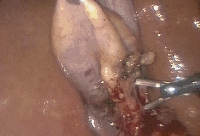

Πρόκειται για άνδρα ασθενή 46 ετών, ο οποίος υποβλήθηκε σε υπερηχογράφημα άνω κοιλίας στα πλαίσια διερεύνησης επαναλαμβανόμενων επεισοδίων επιγαστραλγίας με αντανάκλαση στη δεξιά ωμοπλάτη και τάση προς έμετο. Διαπιστώθηκε χολολιθίαση. Υποβλήθηκε σε λαπαροσκοπική χολοκυστεκτομή μονήρους οπής (SILS). Η τοποθέτηση της θύρας ενδοπεριτοναϊκής προσπέλασης έγινε, αντί στη διομφάλια, στην υπομφάλια θέση, εξαιτίας της ύπαρξης συγγενούς ομφαλικού αιμαγγειώματος (εικόνα 1). Χρησιμοποιήθηκαν εύκαμπτα λαπαροσκοπικά εργαλεία (εικόνα 1) με την τεχνική της διασταύρωσης των χειρών. Ο θόλος της χοληδόχου κύστης αναρτήθηκε στο κοιλιακό τοίχωμα με ράμμα. Πραγματοποιήθηκε πλήρης παρασκευή του τριγώνου του Calot (εικόνα 2) και κατόπιν ακολούθησε η διατομή του κυστικού πόρου και της κυστικής αρτηρίας (εικόνα 3). Η αποκόλληση της χοληδόχου κύστης διενεργήθηκε με τη χρήση hook διαθερμίας (εικόνα 4). Το παρασκεύασμα ανακτήθηκε άθικτο (εικόνα 5). Το άμεσο μετεγχειρητικό κοσμητικό αποτέλεσμα φαίνεται στην εικόνα 6. Έκτοτε ο ασθενής παραμένει ελεύθερος συμπτωμάτων.